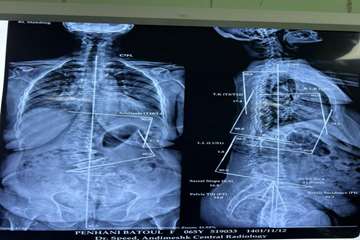

دکتر احمد جباری در توضیح عمل دوم گفت : انحراف در ستون فقرات یا اسکولیوزتوراکولومبار یعنی انحراف در وسط و پایین کمراست  که مهره ها کاملا حول محور افقی و عمودی ستون فقرات یعنی در هر دو محور پیچیده می شود و چون  اصلاح بسیار سخت و عمل ظرافت بالایی دارد جزء عمل های بسیار پیچیده ستون فقرات می باشد که شکرخدا توانستیم بدون هیچ عارضه ای در این عمل 9 مهره را پلاتین گذاری کنیم ،انحراف به وجود آمده را برطرف کرده،دردهای بیمار بهبود پیدا کرده و در نهایت عمل رضایت بخشی انجام شد.